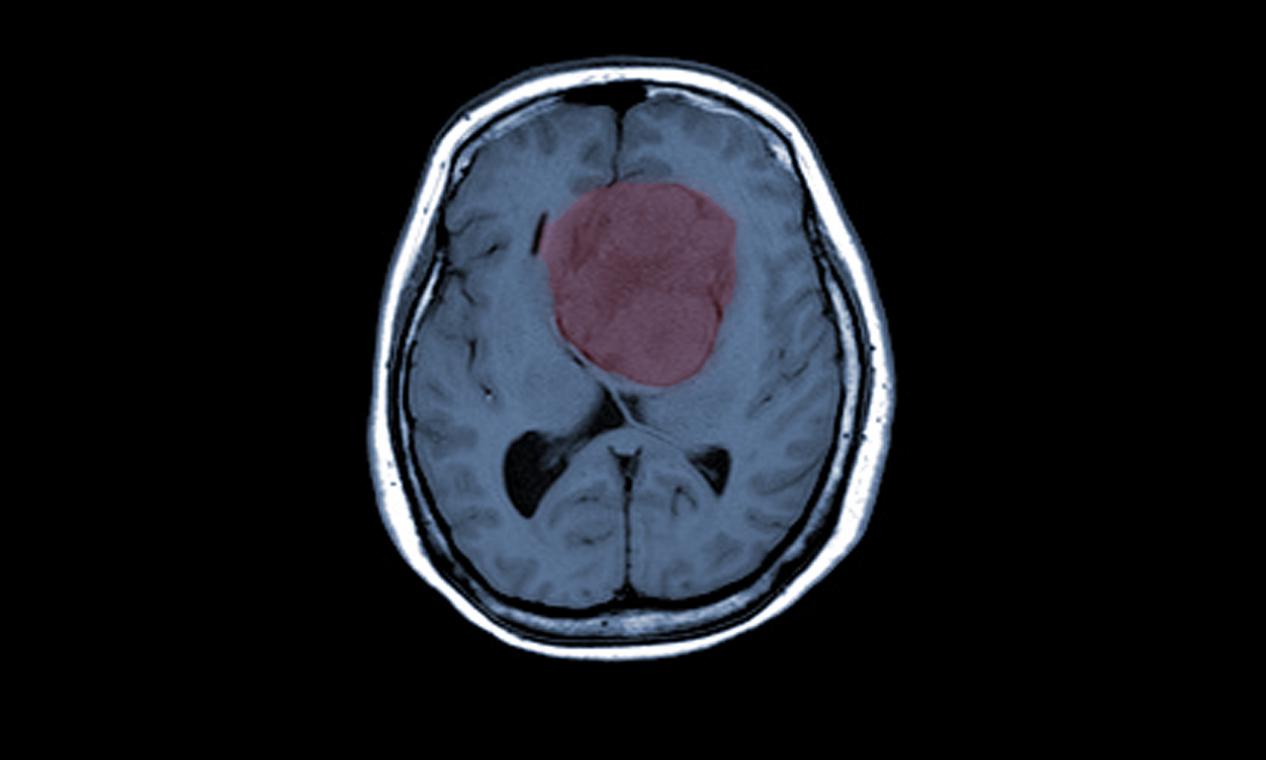

脑膜瘤放射治疗医院,昆明脑膜瘤医院哪家好-昆明医科肿瘤医院脑膜瘤是一种生长在脑膜上的肿瘤,它可能是恶性的也可能是良性的。对于一些较大或难以手术的脑膜瘤,放射治疗可能是一种有效的治疗方法。本文将介绍脑膜瘤放射治疗的原理、过程、风险和预后。脑膜瘤放射治疗的原理脑膜...

脑膜瘤的早期症状,昆明脑膜瘤医院推荐-昆明医科肿瘤医院脑膜瘤(Meningiomas)是起源于脑膜及脑膜间隙的衍生物,发病率占颅内肿瘤的19.2%,居第2位,女性:男性为2:1,发病高峰年龄在45岁,儿童少见。许多无症状脑膜瘤多为偶然发现。脑膜瘤是一种起源于脑...

脑膜瘤的临床表现,昆明脑膜瘤医院哪家好-昆明医科肿瘤医院脑膜瘤是一种常见的颅内肿瘤,它通常发生在脑膜(覆盖脑部和脊髓的薄膜)上。由于它的位置和生长速度不同,其症状和表现也会因个体差异而有所不同。但是,一些常见的症状和诊断方法可以帮助医生和患者及时发现和治疗脑膜...

脑膜瘤放射治疗医院,昆明脑膜瘤医院哪家好-昆明医科肿瘤医院脑膜瘤是一种发生在脑膜(脑部外层覆盖的薄膜)上的肿瘤。它通常是良性的,但在某些情况下也可能是恶性的。脑膜瘤的治疗通常需要一个综合治疗方案,其中包括手术切除、放射治疗和化疗。放射治疗是一种常用的治疗方法,...

脑膜瘤放射治疗效果,昆明脑膜瘤医院哪家好-昆明医科肿瘤医院脑膜瘤是一种比较常见的颅内肿瘤,通常生长缓慢,但如果不及时治疗,可能会对患者的生命和健康造成严重威胁。目前,放射治疗被广泛应用于脑膜瘤的治疗中,已经成为治疗脑膜瘤的重要手段之一。放射治疗通过高能量的放射...